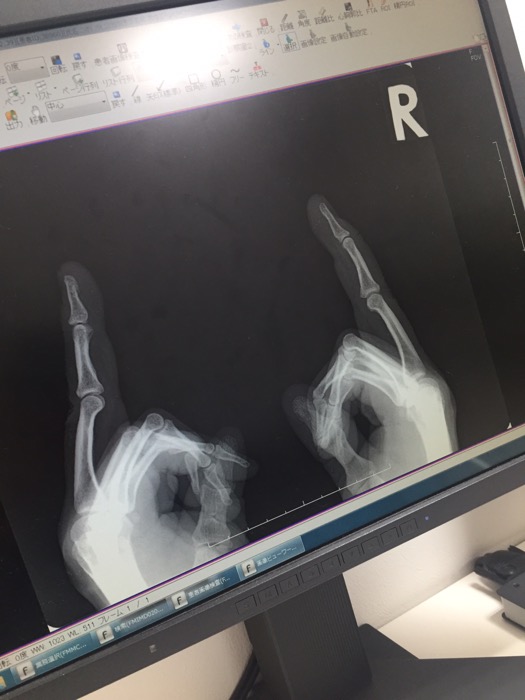

ず

ーっと痛いと思っとたら

指のけん切れとうしーー。

指運無いわー。